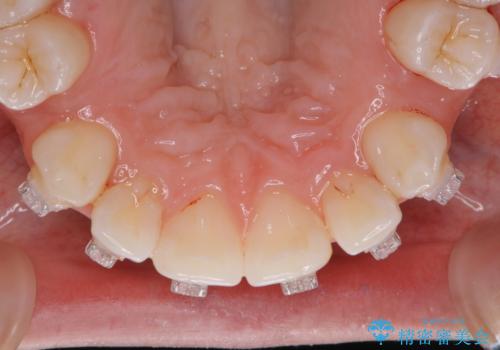

- 審美装置でのワイヤー矯正中の方です。月に1度の調整の際に一緒にクリーニンングもしてほしいとのことでした。

ワイヤーを上下外して、PMTC60分コースを行いました。

矯正治療中も清潔な口腔内を保つことは、とても大切です。そのため、定期的に専門的な機械・材料を使用したProfessinnalcleaning(pmtc)を行うことがおススメです。